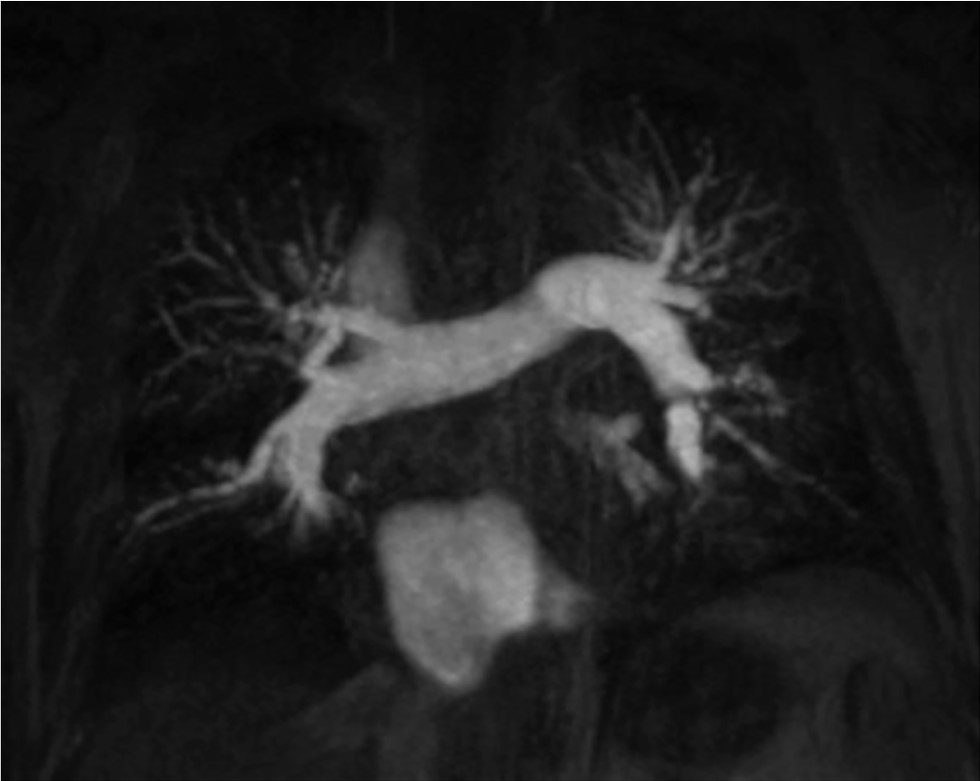

При тромботическом повреждении артерий наибольшие трудности возникают при визуализации дистальных отделов, пристеночного и фрагментарного расположения. С помощью динамического контрастирования возможна оценка микроциркуляторного русла (рис. 6). Бассейн сосудистого русла тромботически поражённой артерии представлен в виде участка с обеднением сосудистого рисунка пониженной интенсивности. Существуют работы, подтверждающие успешное применение МР-ангиопульмонографии в диагностике ТЭЛА у пациентов с промежуточным и высоким риском развития ТЭЛА по данным ЭхоКГ [53, 54]. Таким образом, проведение МР-ангиопульмонографии позволяет избегать применение вентиляционно-перфузионной сцинтиграфии, а также йодной и лучевой нагрузки.

Рис. 6. Результаты магнитно-резонансной ангио-пульмонографии: на изображении во фронтальной проекции определяются расширенные и деформированные лёгочные артерии с пристеночными дефектами контрастирования. Публикуется с разрешения правообладателя. © ФГАУ «Лечебно-реабилитационный центр», 2018.